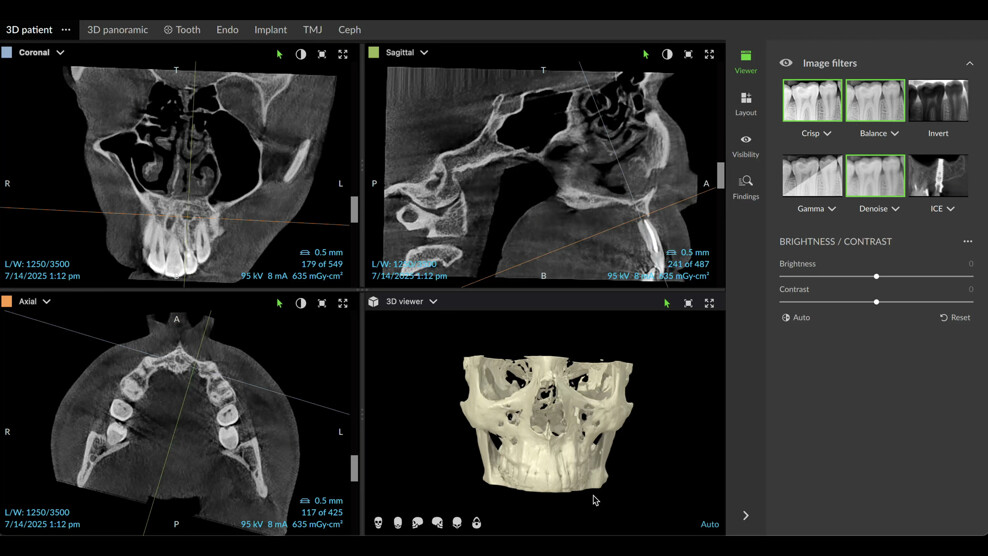

The patient presented for assessment of a fistula in the anterior maxilla on a radiograph, appearing as a large lesion above the lateral incisor (Fig. 1). The patient recalled having been hit by a ball a long time before. A CBCT scan was taken, and it showed a large cystic lesion destroying a large portion of the anterior maxilla. Owing to the edge-enhancing capability of the DTX software provided by artificial intelligence, we can enhance the quality of the image. Since the CBCT scan was taken in a different centre, we imported the DICOM file into the DTX software. The image clearly showed the nerve entering the central incisor and a thin layer of bone covering the apex, and the nerve and periodontal ligament in this area were intact (Fig. 2).

Fig. 2a: CBCT images showing the size of the lesion and destruction of both cortical walls. Artificial intelligence-enhanced image.

At the two-year follow-up appointment, the radiograph showed healing, but there appeared to be a superimposed image at the apex (Fig. 5). A high-definition CBCT scan taken with the DEXIS OP 3D showed that this was not a lesion but fibrous tissue consistent with physiological healing from the palatal area where the cortical plate had been largely damaged (Fig. 6). Since this was not pathological but a normal reparative process, there was no need to interfere.

Fig. 6: High-definition CBCT scan with the DEXIS OP 3D showing fibrous tissue above the root.